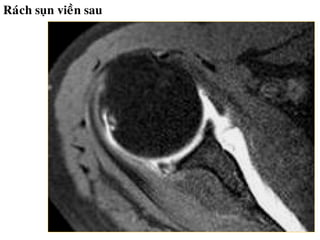

Toån thöông suïn vieàn

- Bình thöôøng, suïn vieàn coù tín hiệu thấp

treân tất cả caùc chuỗi xung.

- Raùch suïn vieàn: bieán daïng suïn vieàn, coù

ñöôøng tín hieäu dòch beân trong suïn vieàn.

- Löu yù bieán theå bình thöôøng cuûa suïn vieàn.

• - MRI thường quy khoù ñaùnh giaù toån thương

suïn vieàn. Toån thương suïn vieàn tröôùc: ñoä nhaïy

44-95% , ñoä ñaëc hieäu 67-86%.

• - MR Arthrography coù ñoä nhaïy 90% vaø ñoä

ñaëc hieäu 95%.

Raùch suïn vieàn sau